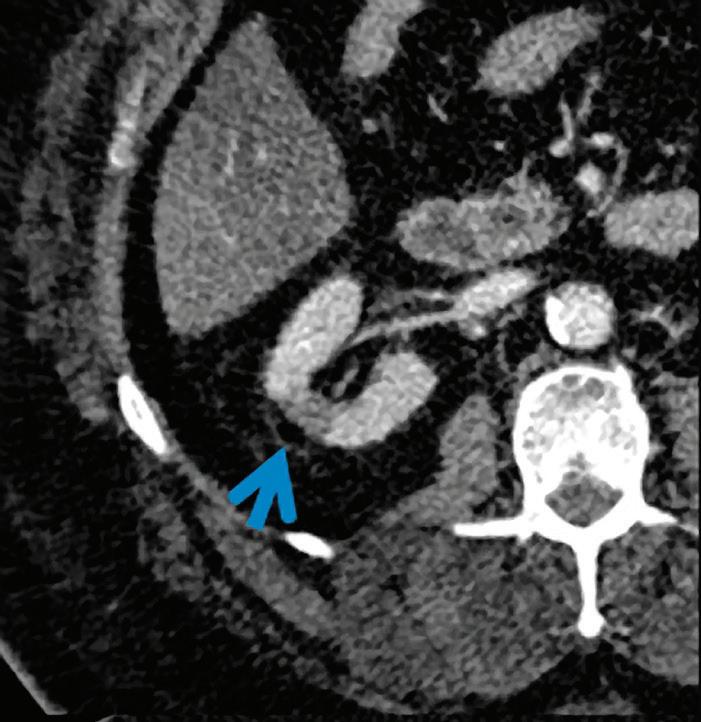

In summary, with the dual-layer detector technique, spectral CT information can be retrieved from any conventional CT scan, without compromises to image quality or needed modifications to scan protocol parameters (rotation time, FOV, dose modulation, etc.), provided the scan is performed at 120 kVp or 140 kVp.9 Spectral analyses from scans at lower tube voltages still pose technological challenges because of the reduced high energy content of the X-ray beam. The reconstruction of selected spectral CT results from a 120 kVp or 140 kVp scan can be decided prospectively, but can also be obtained retrospectively for every scan. This additional information can be used to fine-tune the diagnosis in the case, for example, of an incidental finding. A missed injection is another typical scenario which cannot be known prospectively, but where diagnosis could be salvaged thanks to the available retrospective spectral reconstruction from the original scan without the need to re-inject and re-scan the patient (Figure 2).